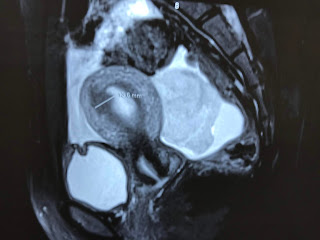

MRI 1 of abdomen detected one mass at right ovary.

MRI 2= sagittal scanning of pelvis, retrouterus bleeding.

MRI 3= frontal view of right/left ovaries, bleeding from right ovary.

Diagnosis is bleeding from right ovary in Mittelschmerz syndrome.